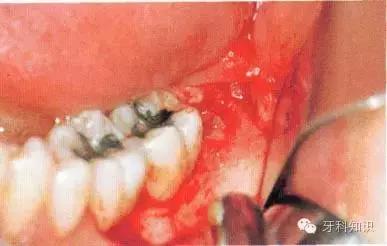

阻生牙拔除术:

手术操作:基本原则

例一

a第Ⅱ类,b分类中位阻生。左下颌第三磨牙阻生,位于黏膜下。磨牙后区切开后,作近中切口,使用12号刀片沿牙龈扇贝状外形切透龈沟至牙槽嵴顶,避免将龈乳头切除。图中近中切口延长至第二前磨牙,便于翻瓣,更好地显露磨牙后区的骨质

b翻瓣后,阻生牙的(牙合)面位于第二磨牙颈部及其牙槽嵴顶均清晰可见。切割牙体前先去除舌侧骨板以保护软组织